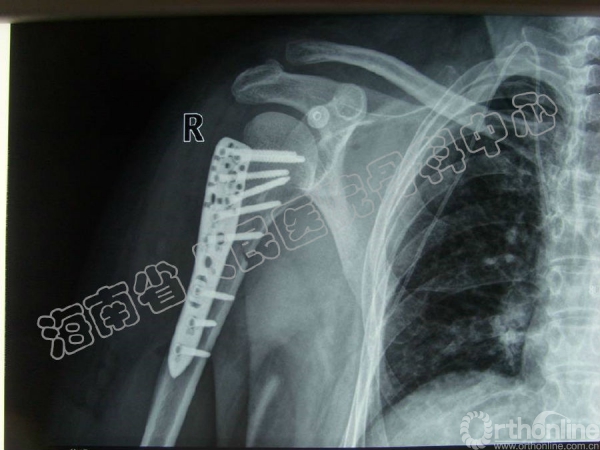

2014-04-14 文章来源:海南省人民医院骨科中心 沈宁江 我要说